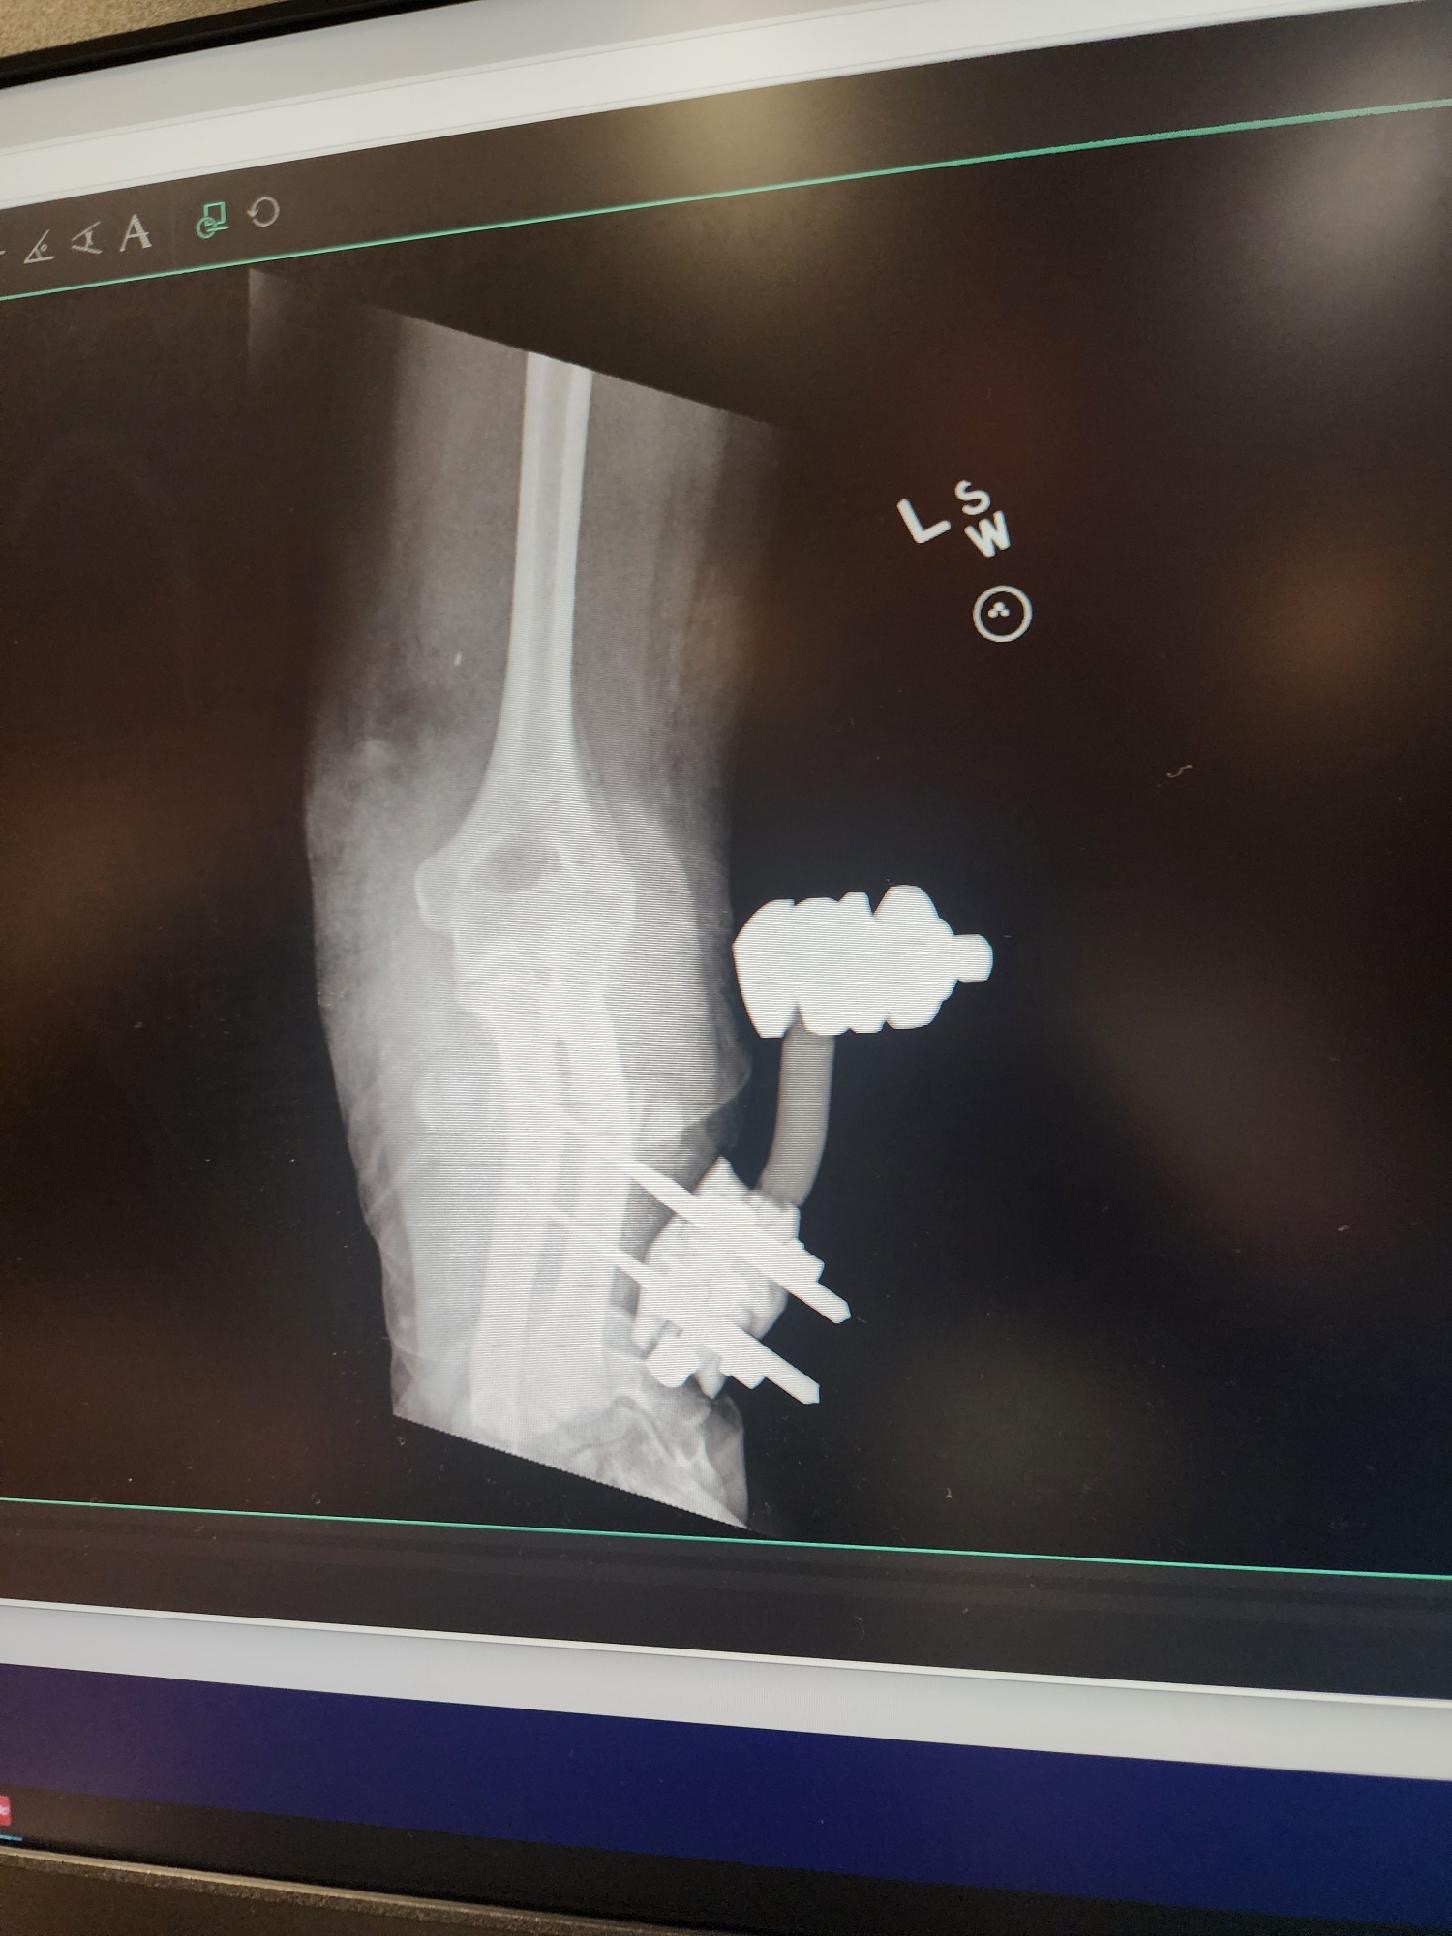

On May 14th 2025, Kaylie was in a horse riding accident resulting in a traumatic arm injury that almost took her life.

So far, surgery has been a success. The medical staff in Billings was able to reconstruct Kaylie’s brachial artery via a graft from her leg, and did their best to put everything back where it belonged.

The next few weeks are pivotal for her recovery. Looking forward, she will undergo multiple surgeries over the next few months to repair ligaments, tendons, etc.